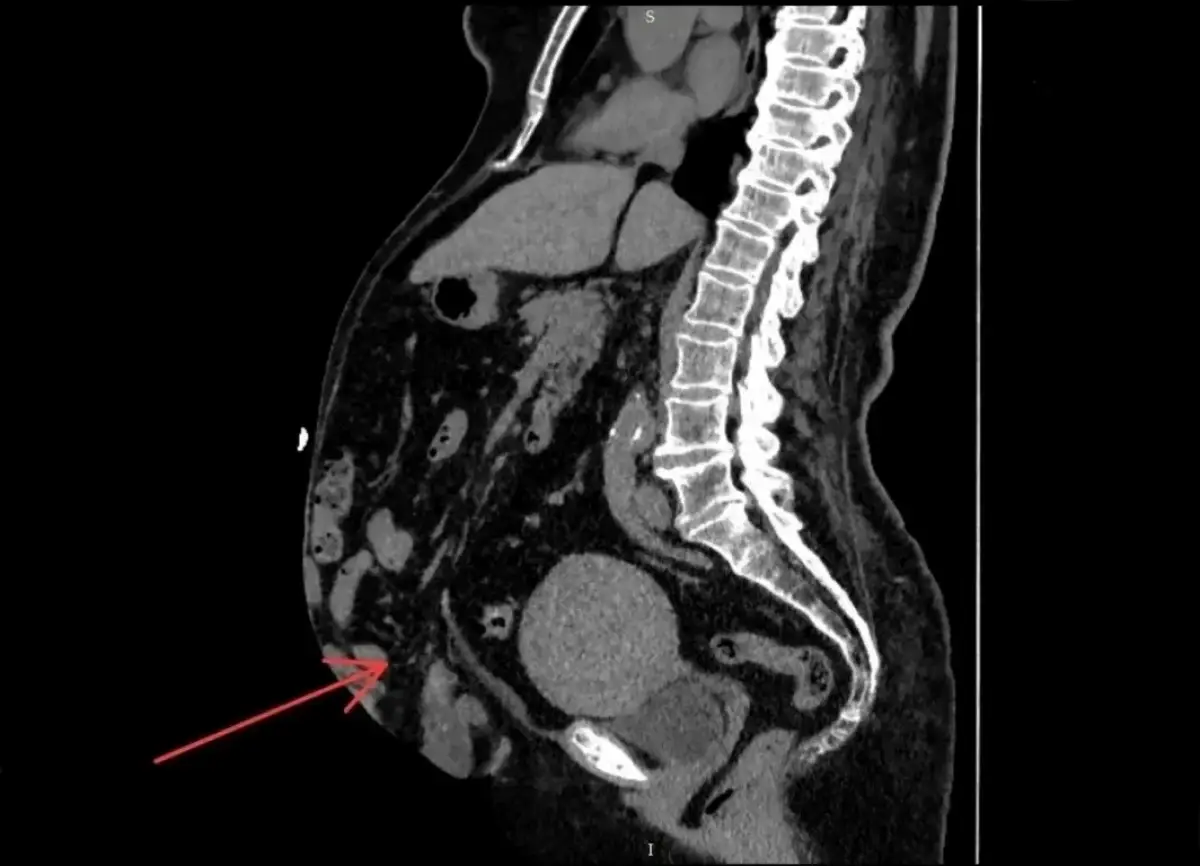

Результаты компьютерной томографии показали, что грыжа достигла 41% от объема брюшной полости. Такое состояние называется потерей домена.